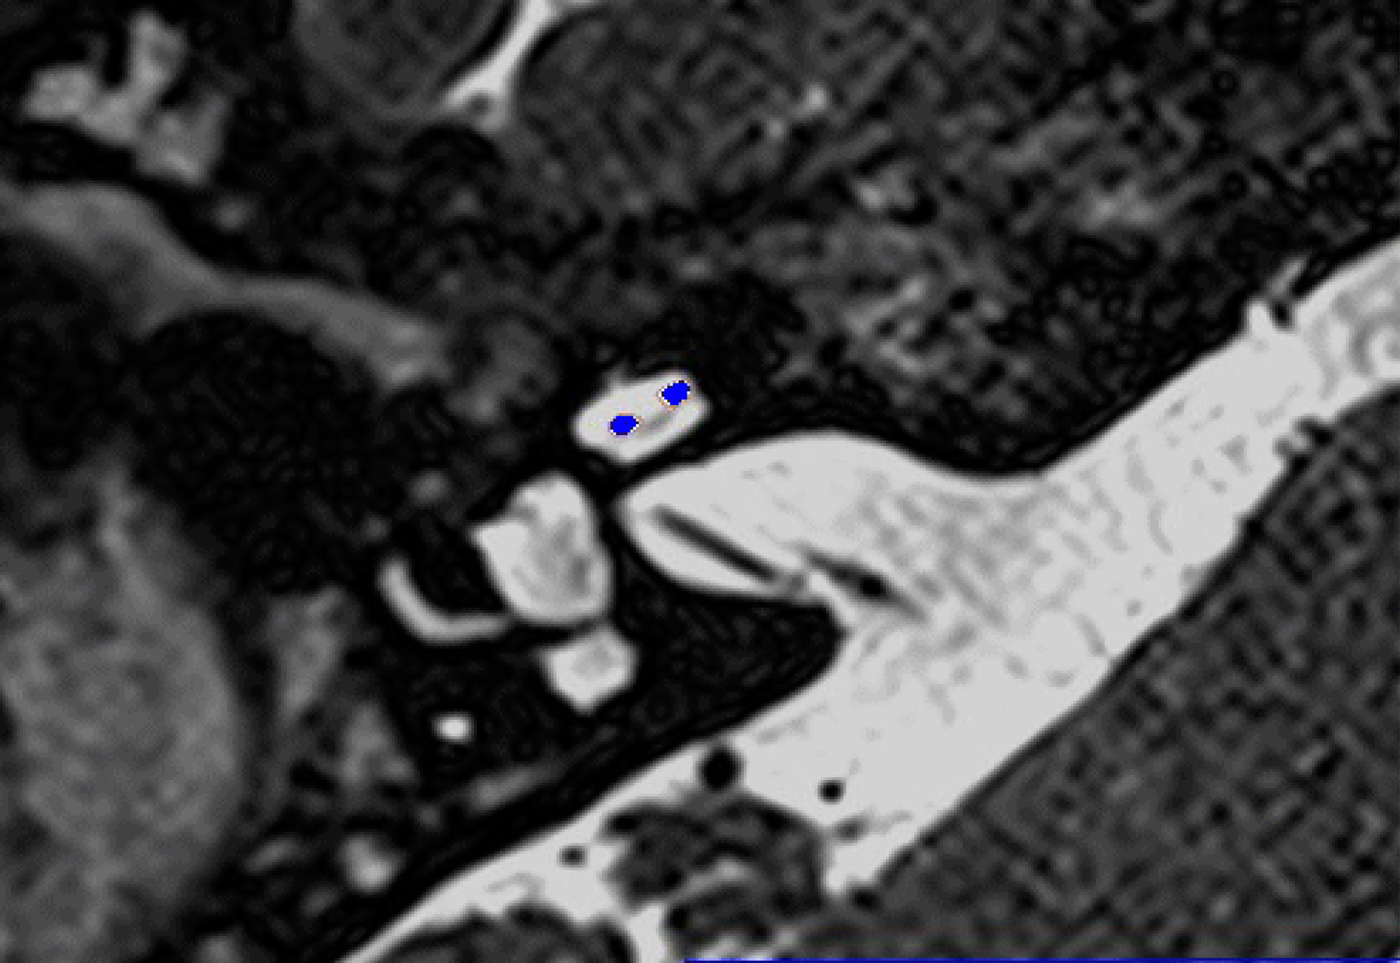

In these 19 cases, co-registration of the pre-operative MRI and post-operative cone-beam CT was performed, as described elsewhere.Reference Dragovic, Stringer, Campbell, Shaul, O'Leary and Briggs8 In short, the cone-beam CT and MRI scans were imported into the image analysis program Amira™ for semi-automatic registration. Three reference points on each image set were marked in three dimensions to allow automatic multipoint registration. The final registration was performed freehand, to ensure that the cochlea, vestibule and semicircular canals were aligned, with researcher satisfaction determining the final endpoint. This allowed accurate assessment of electrode position for these cases (Figures 1–3).

Fig. 2. Co-registered image of pre-operative magnetic resonance imaging and post-operative cone-beam computed tomography scans showing the electrode within scala vestibuli.